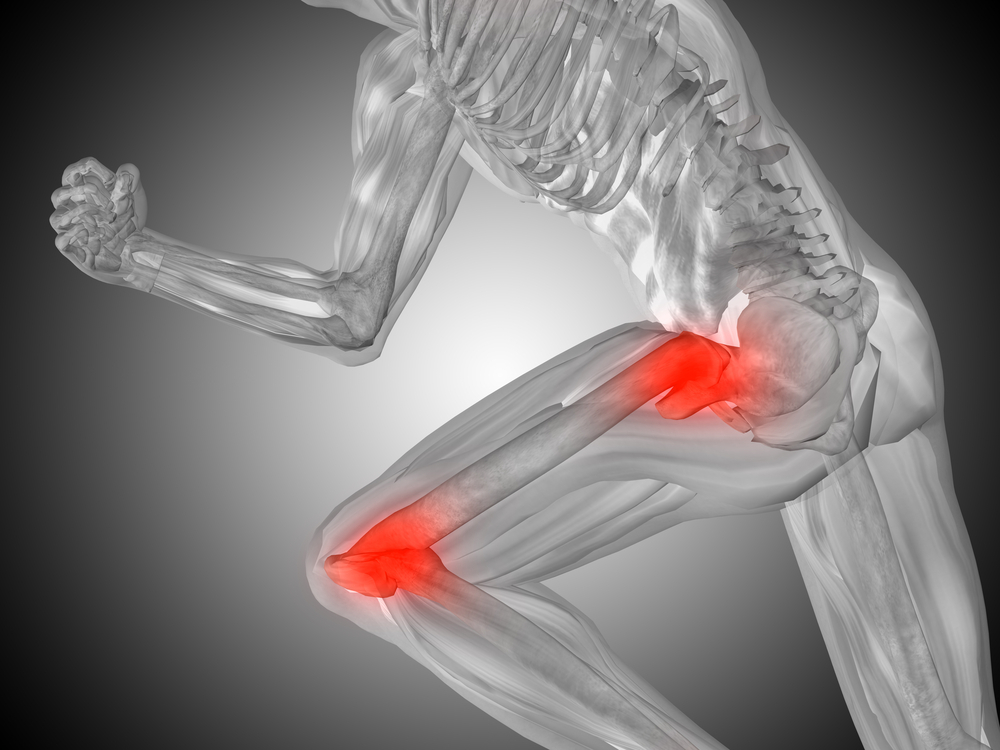

Joint pain can significantly impact your quality of life, limiting movement and making everyday activities challenging. At Fatade Health & Medical Center in Martinsville, VA, we offer joint injections as an effective treatment option to reduce pain and inflammation, helping you regain comfort and mobility.

Joint injections can provide significant relief for various conditions, including:

- Osteoarthritis: Degenerative joint disease affecting knees, hips, shoulders, and other joints.

- Rheumatoid Arthritis: An inflammatory autoimmune disease.

- Bursitis: Inflammation of the bursae (fluid-filled sacs that cushion joints).

- Tendinitis: Inflammation of tendons.

- Gout: A form of inflammatory arthritis.